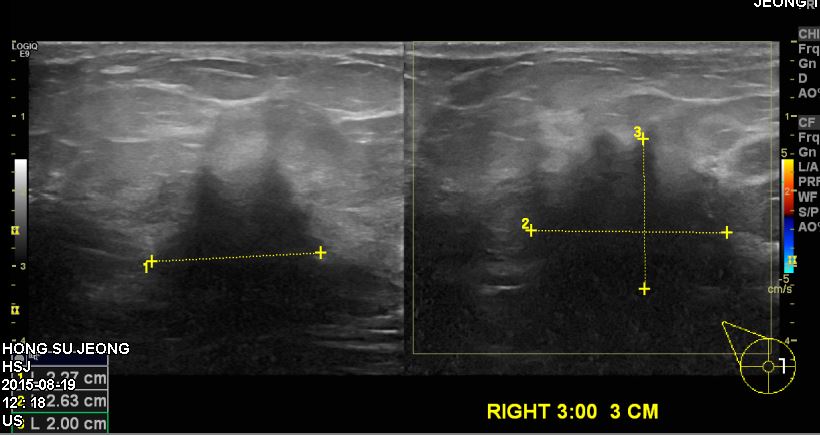

상기환자 60대 여자분으로 10일전 유방에  멍우리 발견하여 본원진료후  우측 3시방향

조직검사 시행한후, 우측유방 침윤성 유관암 진단되셨습니다